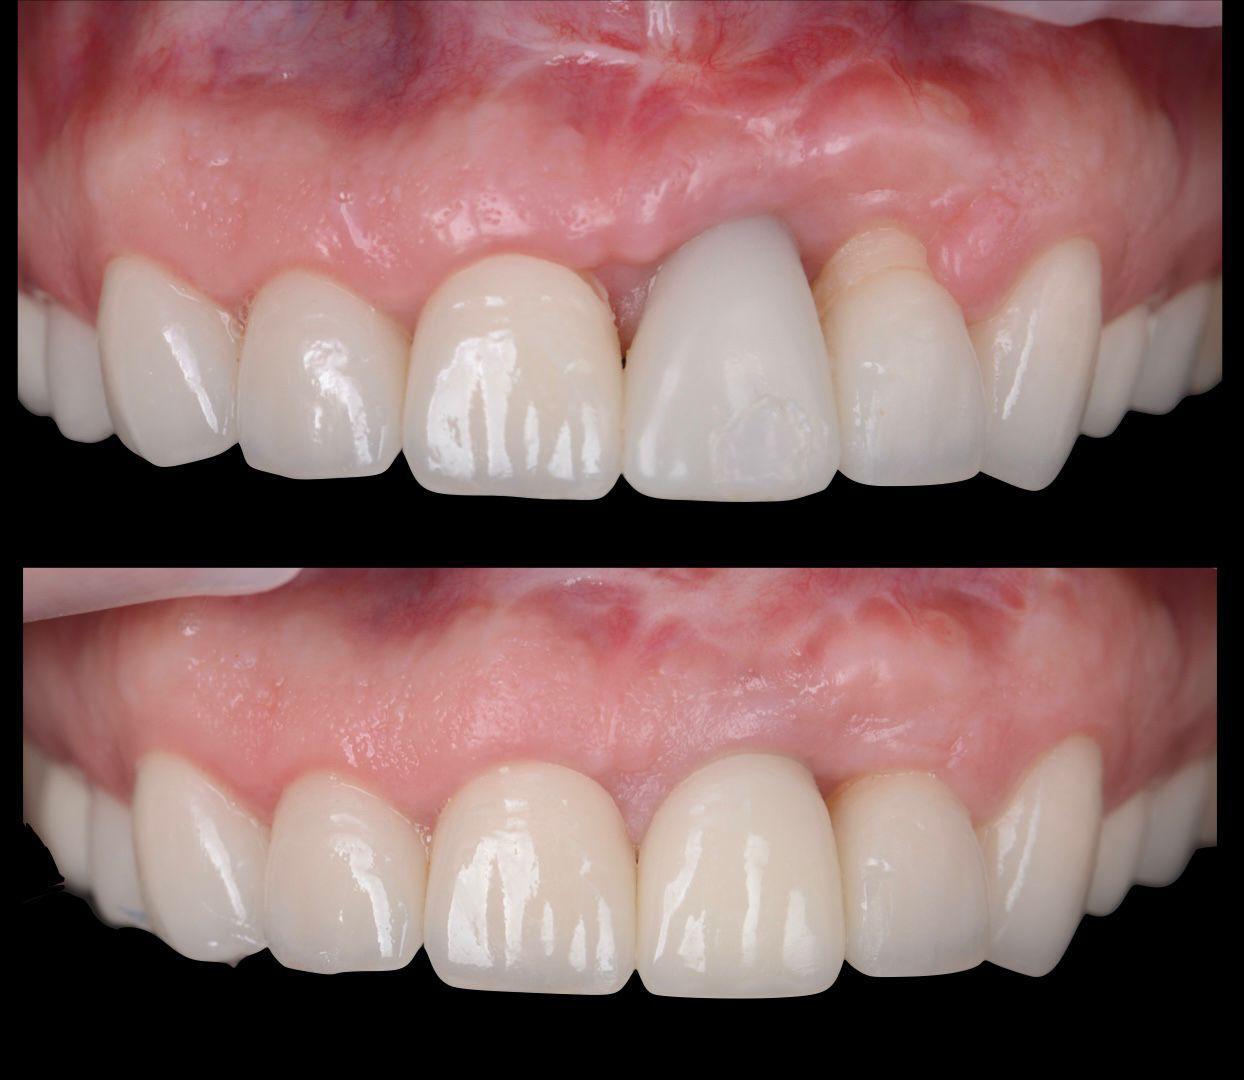

Татьяна Демьяновна Ковалёва

Имплантация. Принципиальное значение костной и мягкой тканей

До

После